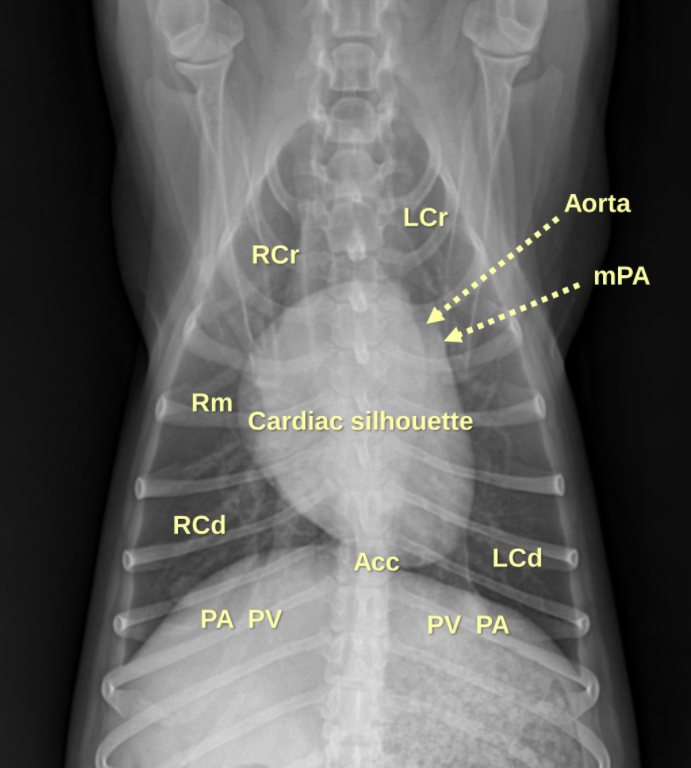

1. Normal Anatomy